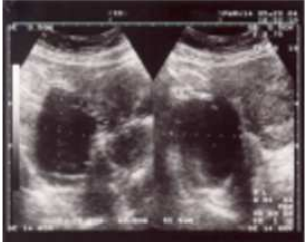

31.32歲女性,主訴近年來經痛越來越嚴重,並有性交疼痛及非經期的腹痛。超音波的檢查如圖所示。下列何者 對於確認診斷最有幫助?

(A)腹腔鏡 (B)比較經期中與非經期的血中CA-125濃度 (C)詳細的病史及理學檢查 (D)子宮輸卵管攝影